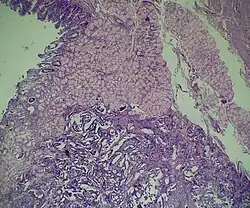

![]() Микропрепарат нейроэндокринной опухоли кишечной стенки. | |